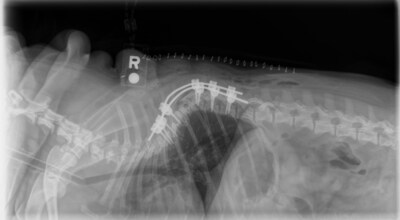

Bài giảng và Đối thoại bàn tròn cấp chuyên gia: Các chủ đề bao gồm phẫu thuật nội sọ, tái tạo hộp sọ, các kỹ thuật phẫu thuật thần kinh ít xâm lấn, cơ sinh học cột sống, ra quyết định cấy ghép, các chiến lược phẫu thuật thần kinh so sánh và những tiến bộ trong phẫu thuật thắt lưng-xương cùng.

Ảnh – https://sporttimes.vn/wp-content/uploads/2025/05/Hoi-nghi-dao-tao-thuong-xuyen-moi-tap-trung-vao.jpg